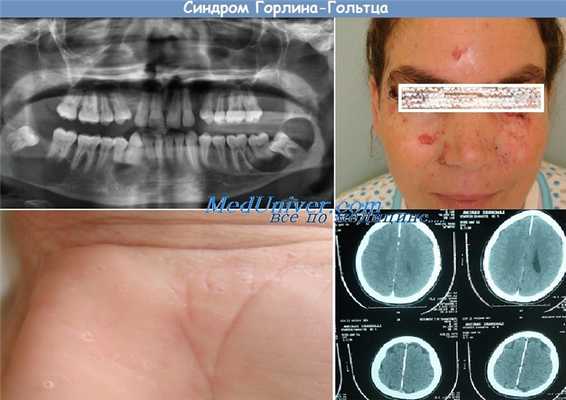

Синдром Горлина—Гольтца (син.: синдром невоидной базальноклеточной карциномы, синдром базальноклеточных невусов) — генетически детерминированный полиорганный синдром, наследуемый по аутосомно-доминантному типу с высокой пенетрантностью и различной экспрессивностью. Мутантный ген локализуется в хромосоме 9 на участке q—22.3-q31. Основное проявление синдрома — множественные базалиомы, которые ассоциируются с разнообразными пороками развития скелета, глаз, нервной, эндокринной систем и других органов и тканей, а также с опухолями различной локализации. Заболевание обусловлено мутациями гена PTSH в хромосоме 9 и ассоциируется с антигенами Н1А-А10, В14. Почти все изменения врожденные.

Базалиомы также могут быть врожденными, хотя чаще появляются в позднем детском возрасте, как правило они развиваются у лиц не старше 35 лет. Обычно это множественные базалиомы, располагающиеся симметрично и билатерально как на открытых, так и на закрытых участках кожи. Преимущественно поражаются лицо, шея, туловище и конечности. Количество базалиом может достигать нескольких сотен. Вначале процесс представлен поверхностными базалиомами диаметром от 1 до 3 см, развивающимися медленно и практически не меняющимися по величине до наступления 2-го или 3-го десятилетия жизни. Затем отдельные новообразования могут быстро увеличиваться до 5-10 см. изъязвляться, под влиянием неблагоприятных внешних факторов среди них появляются кистоз-ные, язвенные формы, а также метатипический рак кожи.

Среди различных костных аномалий, которые имеют врожденный характер и выявляются у 75-90% больных с этим синдромом, наиболее характерны множественные одонтогенные кисты верхней и нижней челюстей которые при нагноении приводят к отечности и тупой боли и могут вскрываться в полость рта. Описываются также кифоз, сколиоз, расщепление ребер, воронкообразная грудная клетка, укорочение IV пястных костей, синостозы, прогнатия, парадонтоз, неправильное расположение зубов, готическое нёбо, срединный носовой синус, широкие носовые ходы, истинный гипертелоризм, выступающие лобные бугры, дизостозы костей лицевого черепа, субкорнеальные кистозные изменения длинных трубчатых и плоских костей.

Аномалии глаз встречаются у 26% больных и проявляются врожденной слепотой, гипертелоризмом, дистопией внутренних углов глаза, катарактой, глаукомой, колобомой, стробизмом.

Поражения центральной нервной системы отмечаются у 10-42% больных и проявляются гидроцефалией, микроцефалией, недоразвитием мозолистого тела головного мозга, пластинчатым обызвествлением серпа большого мозга, кальцификацией твердой и мягкой мозговых оболочек, эпилепсией, деменцией, задержкой психического развития. Патология со стороны эндокринной и половой систем (крипторхизм, гипогонадизм, бесплодие, двурогая матка, фиброматоз яичников, акромегалия, тиреоидит) наблюдается у 17% больных.

Диагноз синдрома Горлина— Гольтца устанавливается на основании совокупности клинико-гистологических данных и результатов обследования стоматологом, челюстно-лицевым хирургом, невропатологом, окулистом, эндокринологом, гинекологом; обязательна рентгенография плоских костей, а для выявления пластинчатого обызвествления серпа большого мозга — рентгенологическое исследование черепа. Дифференциальный диагноз проводят с первично-множественными базалиомами.